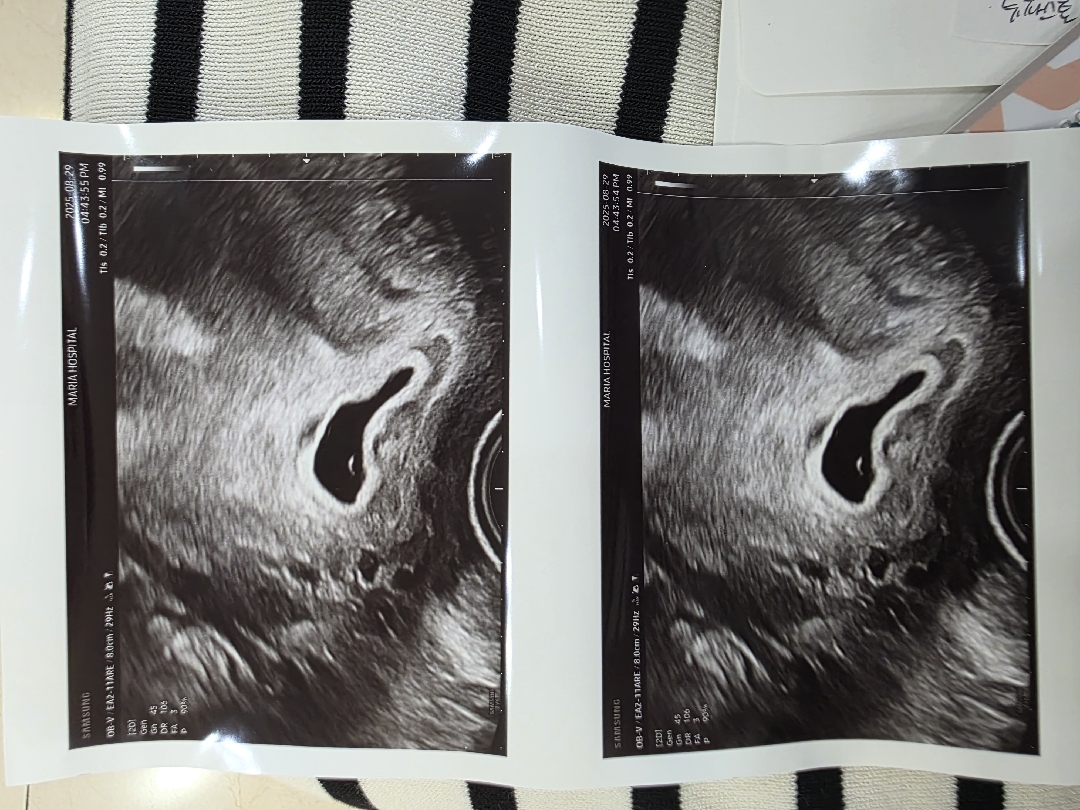

5주차 6주차 초음파 난황 안보임

동결배아 이식후 5주 1일차 쯤 2차피검 5186으로 기쁨도 잠시 5주 3일차 점심때부터 하혈 시작으로 급으로 병원을 갔지만 아기집이 있고 피고임은 없고 타이유 엉덩주사 맞고 일주일뒤 초음파 보자며 주사랑 질정 챙겨서 하루하루 기다리다.... 앞 차수에 출혈후 유산경험으로 겁이나 3일뒤인 5주 6일차 서브병원 초음파릉 봤으나 자궁내 피고임 쪼오금 있었고 여전히 난황은 안보이는 상황... 의사왈 원래 보기로한 수요일날 보눈게 좋을거같다 하여 또 한달같은 4일을 보내고 본병원에서 초음파.. 야간진료라 다른과에서 봤는데... 아직 난황이 안보인다고.. 높은 피검결과였는데 그 수치로는 진행이 잘되어서 잘보여야할시긴데 잘안보이는 소견이다 .. 본과에 다음주에 초음파보고 고사난자일수도있다고......하...... 이상황을 믿을수 없고 대충 봐주는 느낌에 초음파 화질까지 별로 인것같아... 많이 우울해하며 여기저기 5주 6주 초음파 난황 안보임, 고사난자를 엄청 찾아봤지만 안좋은 결과만 있었을뿐!!! 아무리 될놈될이라지만 그래도 ......ㅜㅜ힝 다음주 월욜 본과에서의 초음파 확인을 받아보라는데 월욜까진 도저히 못기다릴거같아서 이틀만에 다시 방문!!!!!! 출혈이나 다른증상으로 왓냐기에...아뇨 ... 초음파상 난황 안보인다던데 다시봐주세요 ㅜㅜㅜ 하고 초음파를 넣었는데 안보였다..... 안보일수도있다고는 하는데... 그래도 좀더 살펴볼게요....하는 찰나 난황이 안쪽에숨어있다고 .....ㅋㅋ 요래저래 캡쳐를 해쥬신다... 안도의 한숨과 눈물이 글썽글썽 ㅠㅠ 못볼뻔 했던 난황은 찾았으니 일주일뒤 다시 보자고한다... 저 처럼 난황이 안보여서 단 며칠을 몇주 몇년같은 시간을 보내며 검색하고 있을 누군가에게 잠깐이나마 응원이 되고싶어 이글을 남겨요!!! 다들 만출 할때까지 한단계한단계 하루하루 잘 질내봐요

겨우 찾았습니다 ㅠㅠ 안보여가지고 ㅠㅠㅠ